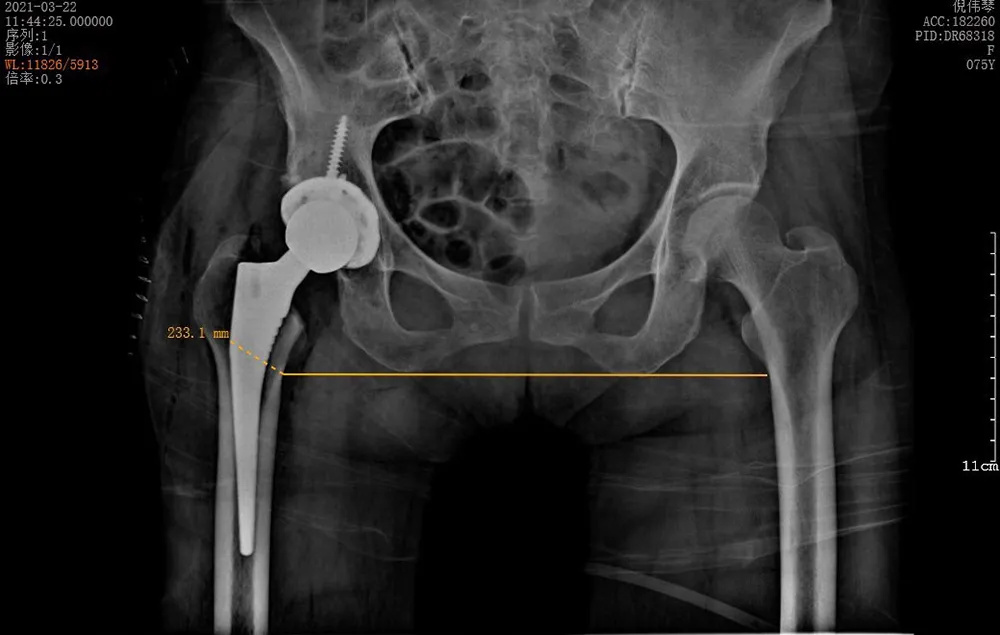

↑術(shù)后雙下肢完全等長